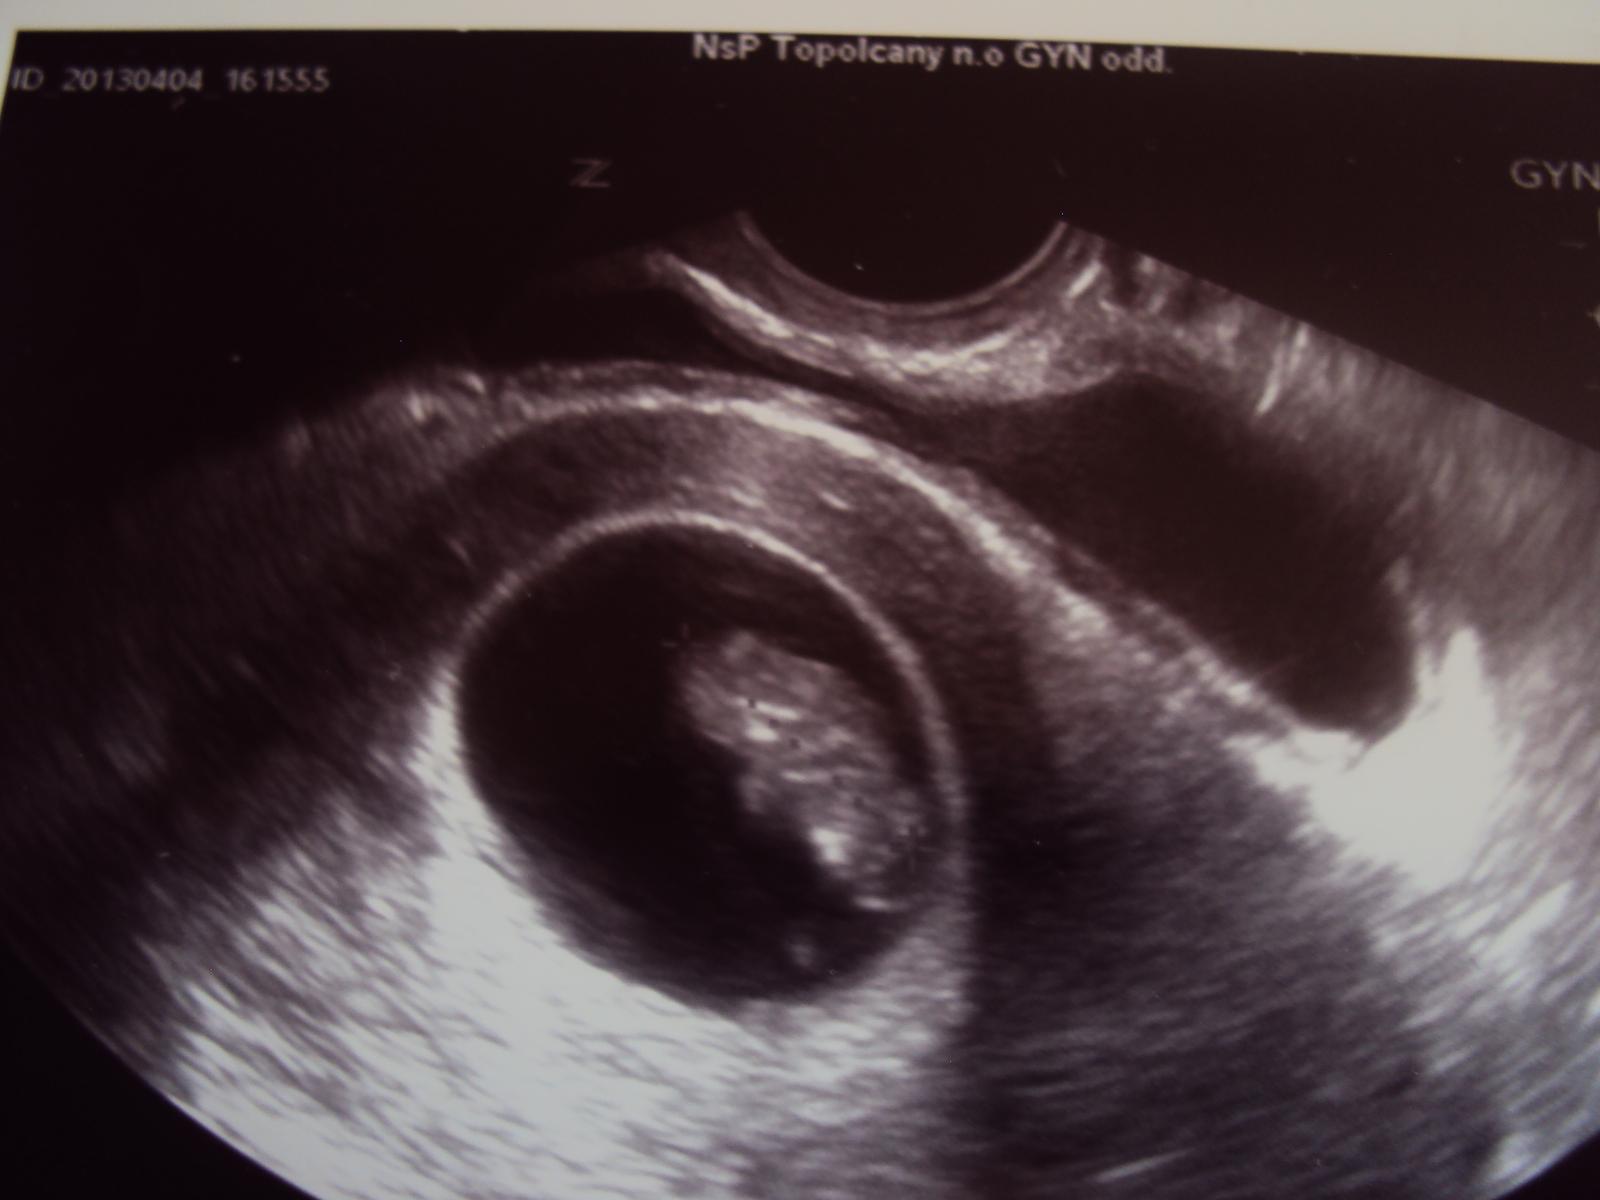

Ahojte, pridavam sa. Termin 21.11.2013 🙂 vcera potvrdeny na UZV

Ahojte, práve som sa vrátila zo sona, všetko je v poriadku, tak sa velmi teším🙂 Srdiečko krásne bije aj mi ho ukázal ako nádherne bije aby som bola spokojná lebo mi dr. povedal, že od strachu som aj dýchať prestala 🙂 Dr. nameral 1,97 cm, ale vravel že sa mu to velmi zle meralo lebo ho nevedel zachytiť, lebo sa drobček hmýril ako zdivočený 😀 Moja dcera je neskutočne štastná lekár ju zavolal dnu na sono a všetko jej ukazoval, tak má užasný zážitok a urobil jej aj dalšiu fotečku.

Ahojte, bola som dnes na ultrazvuku...krpate ma 14 mm a krasne bilo srdiecko 😀 ja si myslim, ze podla ovu by som mala mat termin 24.11. ale doktor mi to bude pocitat podla ms cize 21.11. tak som si to zmenila aj tu. Vraj tomu aj velkost zodpoveda tak ja neviem. Buduci utorok idem na krv a dostanem uz aj knizku 🙂